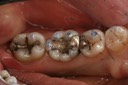

Alan Chinn #3 caries removal 2

Alan Chinn #3 prep